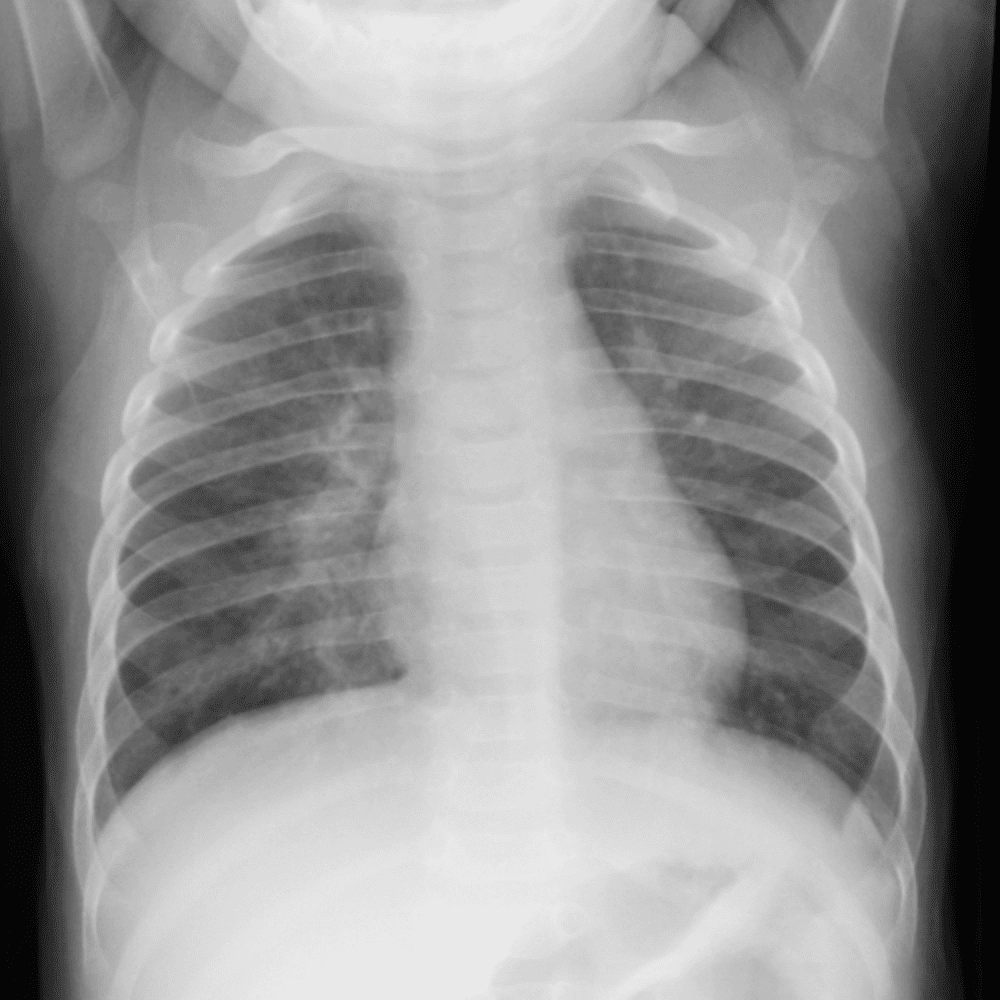

Peds Chest

Practice

Simulates call by including subtle or difficult cases and some normals.

50 cases